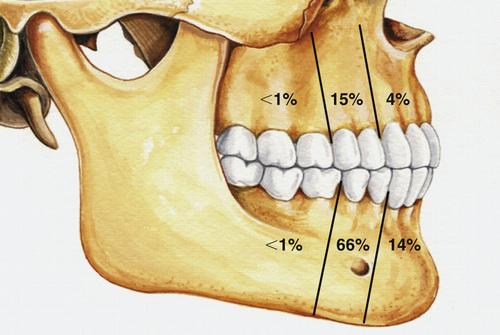

- most often involve mandibular third molars (65%)

- most often occurs in the mandible (60% to 80%)